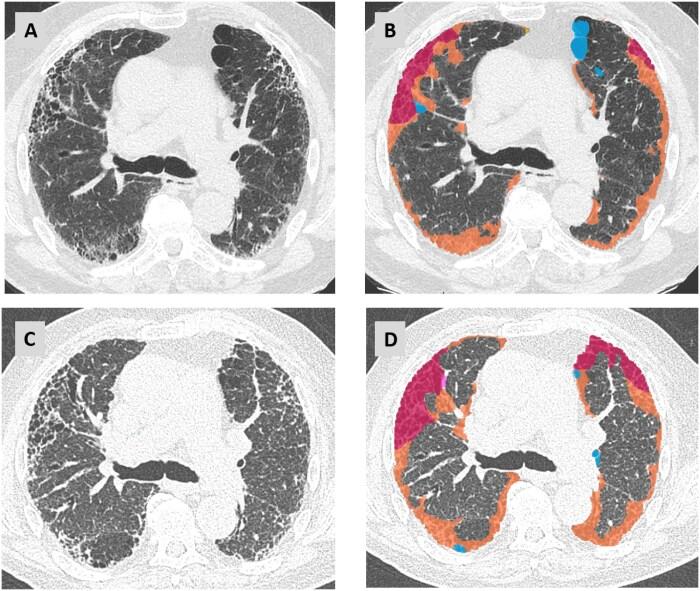

A subset of patients with interstitial lung diseases (ILDs) experiences disease progression despite standard treatment protocols. Similar to idiopathic pulmonary fibrosis, the archetype of progressive fibrotic ILDs, these patients exhibit worsening clinical symptoms, declining lung function, and progressive radiological changes, often resulting in shortened survival. This progressive disease pattern is classified under the term progressive pulmonary fibrosis or progressive fibrosing ILD. Radiological imaging, particularly high-resolution computed tomography (HRCT), is integral to diagnosing ILDs and plays a critical role within multidisciplinary ILD boards. HRCT is instrumental in identifying patients at a higher risk for disease progression and may provide valuable prognostic insights. Additionally, serial imaging is essential for detecting progression over time. While visual assessment remains the primary method for evaluating disease advancement, emerging quantitative techniques, including those utilizing machine learning, are currently undergoing validation.

尽管采用了标准治疗方案,仍有一部分间质性肺疾病(ILD)患者病情进展。与进行性纤维化ILD的原型特发性肺纤维化类似,这些患者表现出临床症状恶化、肺功能下降和影像学改变进展,常导致生存期缩短。这种进行性疾病模式归类为进行性肺纤维化或进行性纤维化ILD。放射影像学,尤其是高分辨率计算机断层扫描(HRCT),对于ILD的诊断不可或缺,在多学科ILD诊疗团队中发挥着关键作用。HRCT有助于识别疾病进展风险较高的患者,并可能提供有价值的预后信息。此外,系列成像对于检测随时间的进展至关重要。虽然视觉评估仍然是评估疾病进展的主要方法,但包括利用机器学习的技术在内的新兴定量技术目前正在进行验证。